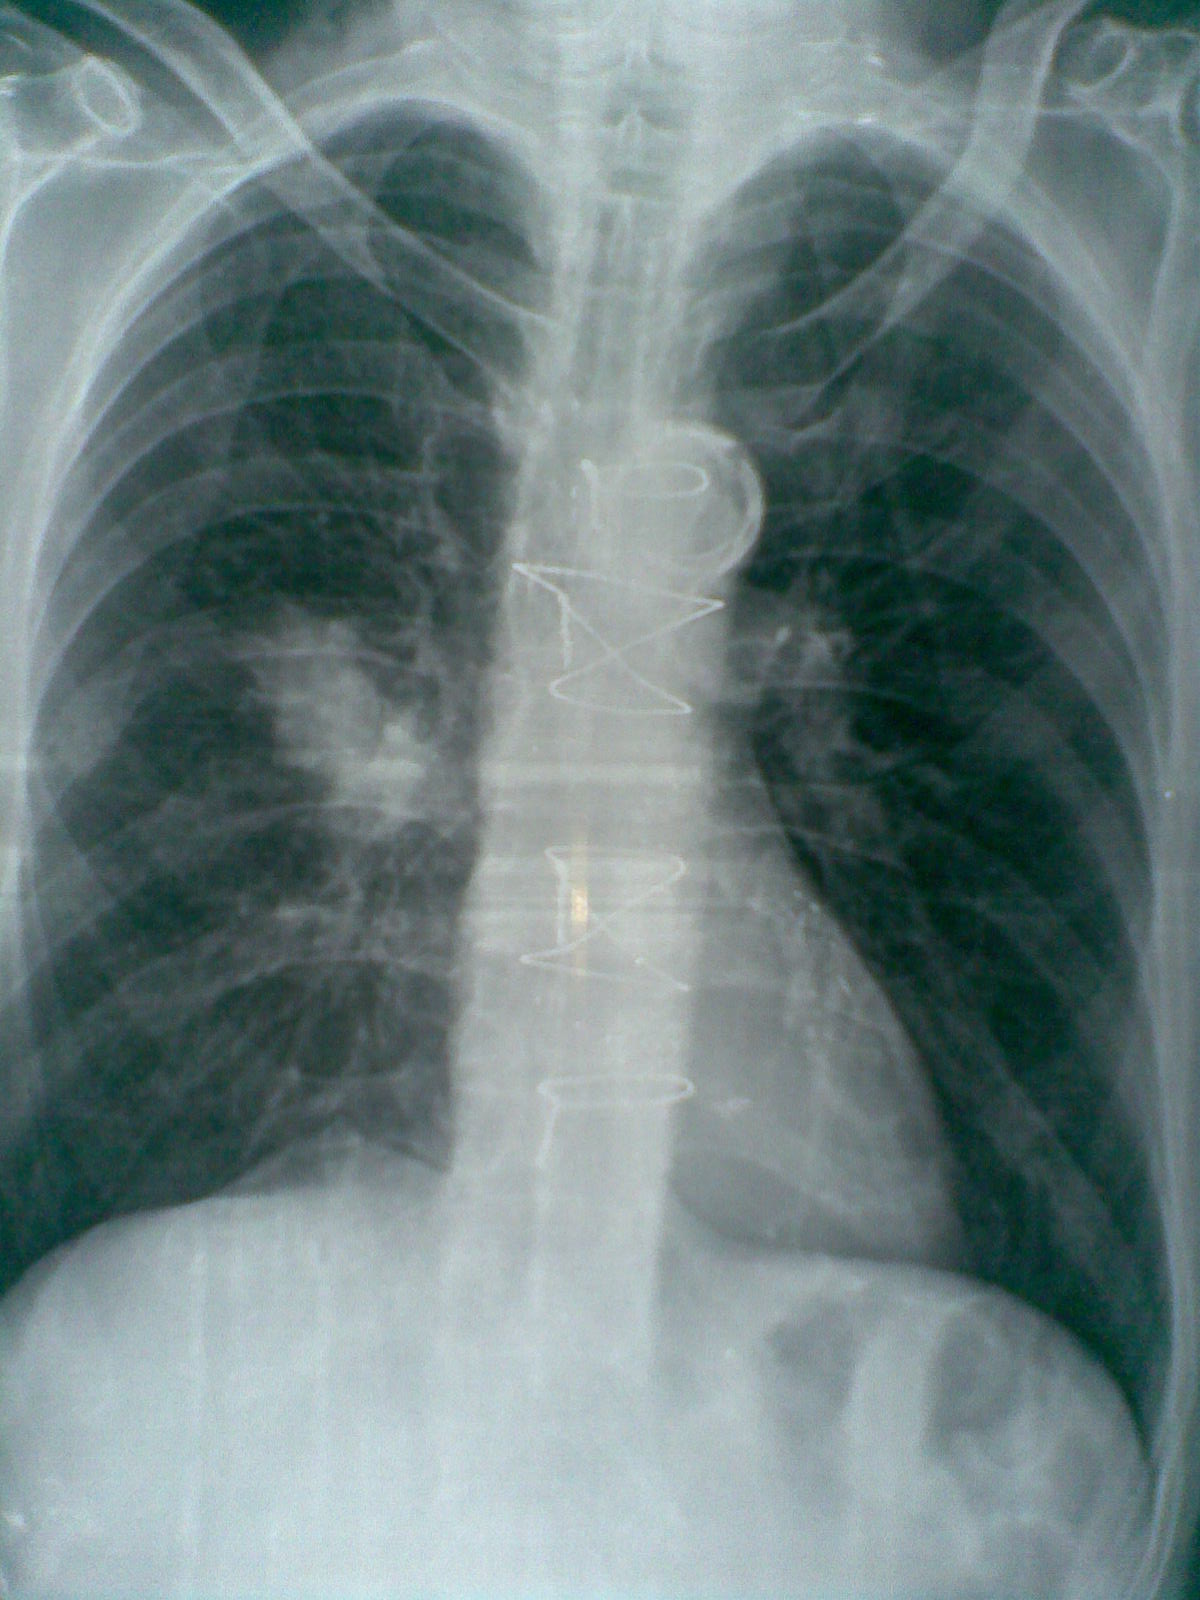

From www.mdpi.com

JCM Free FullText Value of Perioperative Chest Xray for the Post Cabg X Ray Recent data suggest that almost 10% of patients who undergo coronary artery. Coronary artery bypass grafting (cabg) is a major surgical operation where atheromatous blockages in a patient’s coronary arteries are bypassed with harvested. These clips are placed to prevent flow through the branches of the internal mammary arteries which are used to form the coronary artery bypass Patients and. Post Cabg X Ray.